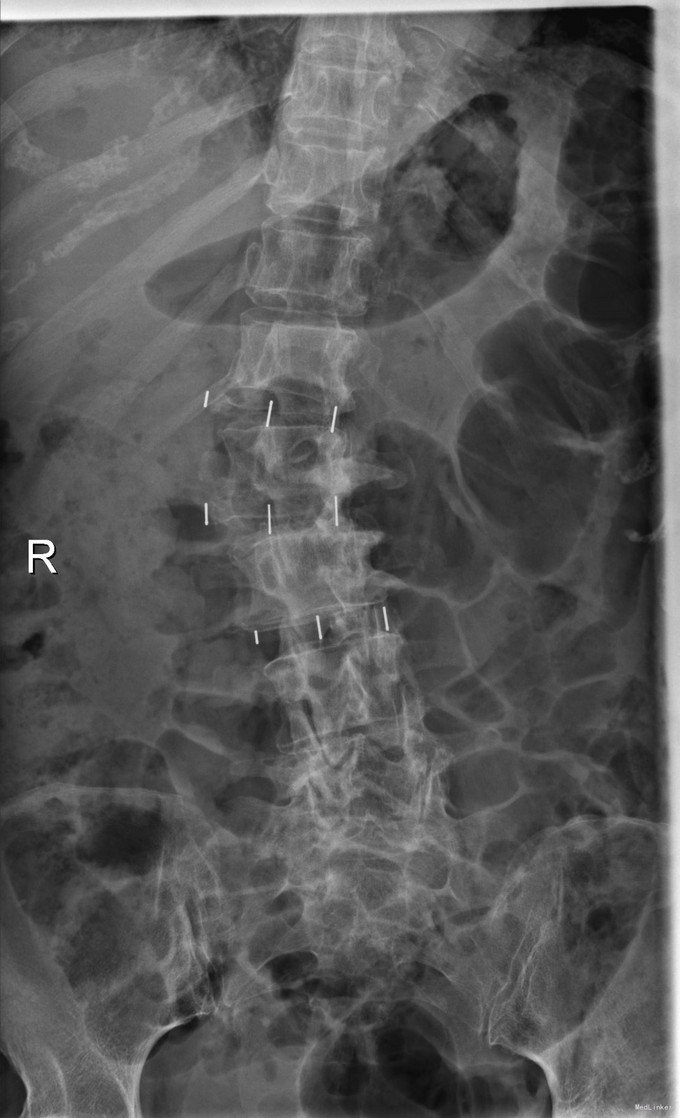

主诉:右下肢麻木11年,腰部酸痛无力 现病史:女性患者,65岁,患者于11年前无明显诱因下出现右下肢麻木,自大腿至右踝部,站立位加重。未予重视,后期出现腰臀部僵硬,弓背僵硬无力,自主行走距离不足200米,曾于06年经X线平片及MRI检查:腰椎椎管狭窄伴有腰椎滑脱,椎间盘突出等。

查体:侧弯畸形,右臀部及右下肢麻木疼痛,腰部活动受限,难以站立。右侧支腿抬高试验60°。双下肢肌力肌张力可。 辅助检查:平片:腰椎侧弯,椎体滑脱,曲度后凸 磁共振:L2-3,L4-5,L5-S1腰椎椎管狭窄,l2-3L3-4L4-5L5-S1腰椎间盘突出,腰椎退变

诊断: 腰椎侧弯,腰椎间盘突出 治疗:1期微创侧路椎体融合术+2期 微创后路经皮内固定术